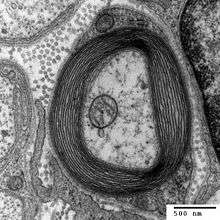

Transmission electron micrograph of a cross-section of a myelinated axon, generated at the Electron Microscopy Facility at Trinity College, Hartford CT

Myelin is made by different cell types, and varies in chemical composition and configuration, but performs the same insulating function. Myelinated axons are white in appearance, hence the "white matter" of the brain. Myelin helps to insulate the axons from electrically charged atoms and molecules. These charged particles (ions) are found in the fluid surrounding the entire nervous system. Under a microscope, myelin looks like strings of sausages.